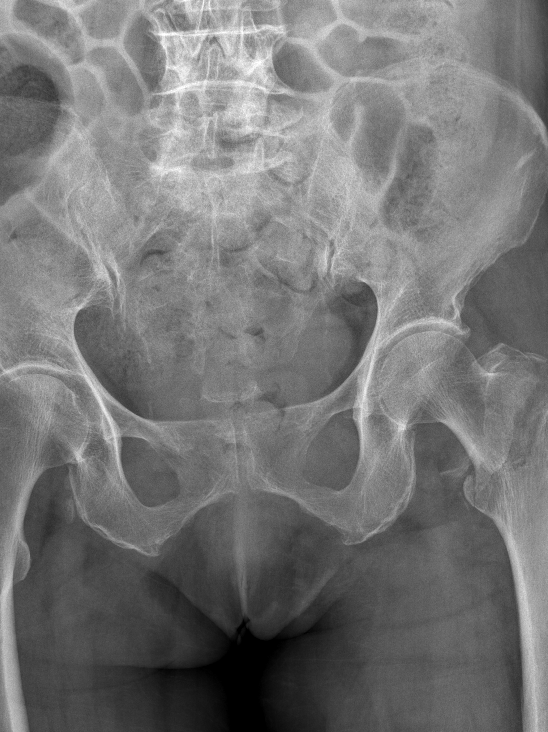

4月23日,贵州航天医院第58次晨读会由我院骨科副主任医师张艳金作学术交流,他以“加速康复指导下的快速手术”为题,详细讲解了老年股骨粗隆间骨折与儿童四肢骨折的临床诊疗难点,结合加速康复外科(ERAS)核心理念,重点阐述了ERAS理念在两大人群中的创新实践,实现患者入院后6至24小时内即可接受手术治疗。针对老年髋部骨折患者,提出通过多学科协作(MDT)与微创手术优化围术期管理,在确保安全前提下缩短术前等待时间,实施精准化麻醉及术后康复方案,可有效降低并发症发生率、改善患者生活质量和预后效果。在儿童骨折领域,强调微创术式与心理干预并行的双轨策略,既减少手术创伤对骨骼发育的影响,同时关注患儿心理疏导,实现生理功能与心理健康同步康复。并通过典型案例的影像学资料与随访数据,直观展示了ERAS理念指导下骨科治疗模式的创新成果。 贵州航天医院骨科 专家简介 赵学平 中共党员,骨科党支部书记、主任,主任医师 临床擅长:从事骨科临床工作30余年,对骨科常见疾病的诊治具有丰富的临床经验。 世界中医药联合会脊柱康复专业委员会常务理事,中华中医药学会整脊分会常务委员,中国中西医结合学会骨伤科分会肢体矫形功能重建与康复专家委员会常务委员,中国研究性医院学会骨科创新与转换专业委员会关节外科学组保髋工作委员会常委,中国康复技术转化及发展促进会骨外科与康复技术转化专业委员会常务委员,泛珠三角区域运动医学联盟(PPRD-SMA)理事会常务理事,中国研究型医院学会运动医学专业委员会委员,贵州省中医药学会整脊分会副主任委员,贵州省中西医结合学会银质针专业委员会副主任委员,贵州省康复医学会骨与关节专业委员会常务委员,贵州省人民医院骨科专科联盟常务理事,贵州省康复医学会骨内科专业委员会常务委员,中华医学会贵州省骨科学会委员,贵州省康复医学会脊柱脊髓专业委员会常务委员,贵州省运动医学分会委员,贵州省康复医学会骨与软组织肿瘤专业委员会委员,遵义市医学会创伤分会副主任委员,贵州省康复医学会骨内科专业委员会遵义地区分会常务委员,遵义市医疗事故鉴定、伤残鉴定、工伤鉴定、司法鉴定专家。 长期从事骨科临床研究及教学工作,在国家级、省部级杂志发表论文20余篇,SCI论文2篇,参与主编骨科专著2部,主持省部级科研项目2项,参与指导省部级、市级科研项目6项。 陈明勇 骨科副主任,副主任医师 临床擅长:从事创伤骨科工作约20年,对骨缺损、骨不连、骨肿瘤、肢体畸形等的肢体矫形重建及功能重建,慢性化脓性骨髓炎的根治治疗、糖尿病足的保肢治疗、快速康复理念(ERAS)下的老年骨折的诊治,四肢复杂骨折的诊治,四肢骨折等微创手术治疗具有丰富的临床经验。 2004年毕业于遵义医学院临床专业,曾在中国人民解放军总医院、广西医科大学第一附属医院、上海第六人民医院骨科进修。中国中西医结合学会骨伤科专业委员会横向骨搬移治疗糖尿病足及微血管网再生学组首届委员,遵义市医学会创伤分会常务委员。 瞿 辉 中共党员,骨科副主任医师 临床擅长:对骨科的常见病、关节外科、脊柱外科及运动医学疾病的诊治具有丰富的临床经验,熟练掌握骨科手术操作技术。 毕业于遵义医学院临床医学系,2005年前往广州中山大学第一附院骨显微医学部进修学习,2011年前往成都华西医院进修学习,并多次在省内外学习骨科相关知识,是中华医学会骨科分会会员。 赵兴东 骨科主任医师 临床擅长:擅长骨科的常见病及各种创伤、四肢骨折创伤修复、骨感染、手足疾病的诊治和手足体表畸形的矫形整复,熟练掌握骨科四肢骨病及创伤的手术操作技术,尤其在四肢关节复杂性损伤、手足外伤、组织缺损创面、难治创面的皮瓣修复方面及平足、高弓足矫形方面及四肢慢性疼痛诊治、康复方面具有丰富的临床经验。 硕士研究生,毕业于遵义医学院临床外科系,2015年前往山东省立医院手足外科进修学习;遵义市医学分会创伤分会第一、二届委员,遵义市手外科医学会第二委届员会常务委员;在省级及省级以上期刊发表文章9篇,参编著作2部,参与主持并完成市级课题1项,参与市级课题2项、省级课题1项。 张艳金 中共党员,骨科副主任医师 临床擅长:从事骨外科工作16年,对复合伤、多发伤的救治、四肢骨干骨折、关节周围骨折、骨肿瘤、骨髓炎等诊治具有丰富的临床经验。 中共党员,硕士研究生,2006年本科毕业于山西医科大学第二临床医学院,2011年研究生毕业于北京军区总医院;在“老年COPD患者合并髋部骨折的诊治”国际合作课题组研究两年,在老年髋部骨折的诊治方面具有丰富的经验,并发表论文6篇;主持遵义市级课题1项,承担遵义医科大学的临床教学工作,获得遵义医科大学优秀带教老师荣誉。编撰有《骨科疾病诊疗精粹》一书,开展2项新技术,编撰地方规范《务川自治县创伤骨科常见疾病诊疗规范》一书。 张俊凯 骨科副主任医师 临床擅长:从事骨科临床工作28年,对创伤骨折、骨感染、骨缺损、骨不连等外科诊治,四肢骨折的微创手术治疗,四肢复杂骨折(如关节内粉碎性骨折、多发骨折等)的损伤控制及手术治疗等具有丰富的临床经验。 1995年毕业于遵义医学院临床专业,2009年前往复旦大学附属医院骨科进修1年。 卢懿明 中共党员,骨科副主任医师 临床擅长:从事骨科工作18年,对创伤骨折、四肢骨折的微创手术治疗、四肢复杂骨折(如关节内粉碎性骨折、多发骨折等)的损伤控制及手术治疗,尤其是髋部骨折的PFNA等微创技术,踝关节骨折、膝关节周围骨折的Mipo微创技术等具有丰富的临床经验,开展了4项新技术,发明6项新型专利技术。 2005年毕业于遵义医学院临床专业,2017年,前往南方医科大学第三附属医院骨科进修半年,回院后运用Mipo技术对骨干骨折及干骺端骨折的治疗技术,同时积极开展骨盆骨折、髋臼骨折腹直肌外侧切口的应用;发表了多篇专业论文,经常参与省内外学术交流会授课,获得医院荣誉称号多个。 邬夏荣 骨科副主任医师 临床擅长:从事骨科工作16年,对四肢复杂骨折、骨肿瘤的诊治,尤其是足踝创伤、慢性踝关节损伤、平足症等诊疗具有丰富的临床经验。 2006年毕业于遵义医科大学临床医学专业,曾在陆军军医大学西南医院进修学习,发表多篇骨科学术论文。 余德怀 中共党员,骨科副主任医师 临床擅长:从事骨科工作10余年,对运动医学、骨关节、脊柱外科常见病、多发病的诊治具有丰富的临床经验。 硕士研究生,2011年毕业于遵义医学院临床医学专业,曾前往遵义医科大学附属医院运动医学专业进修学习;是贵州省医学会运动医学分会青年委员,西部关节镜联盟委员;发表多篇骨科学术论文。 冯 乾 骨科副主任医师 临床擅长:从事骨科工作近20年,熟练掌握骨科多发病及常见病的诊治,尤其对脊柱退变性疾病的诊断及治疗具有丰富的临床经验,主要研究脊柱微创相关治疗方式,能熟练开展椎间孔镜及UBE。 曾前往北京大学第三医院进修学习疼痛及椎间孔镜、首都医科大学友谊医院专业进修脊柱内镜;是贵州省康复医学会第三届脊柱脊髓专业委员会委员;发明专利3项、发表脊柱外科专业论文多篇。 赵小锋 中共党员,骨科副主任医师 临床擅长:从事骨科临床工作11年,对骨科常见病、多发病诊疗有较为丰富的临床经验,擅长脊柱相关疾病诊断及治疗,尤其是颈、腰、腿疼痛疾病诊断及治疗,擅长胸腰椎骨折微创经皮穿刺内固定术、经皮穿刺椎体成形术、经皮穿刺脊柱内镜下腰椎间盘摘除术、单纯开创腰椎间盘摘除术、腰椎滑脱复位椎间植骨椎融合内固定术、腰椎管狭窄减压融合内固定术及人工髋、膝关节置换术等。 2012年毕业于遵义医学院外科学专业硕士研究生,2019年参加“遵义市115医学人才精英计划”于上海交通大学第一附属医院培训学习,2023年于北京大学第三人民医院脊柱外科进修学习,曾获得遵义市优秀医师荣誉称号。 遵义市手外科第一届委员,遵义市医学会创伤分会第一届委员,遵义市医学会创伤分会第二届委员,贵州省康复医学会第三届脊柱脊髓专业会委员,遵义市医学会烧伤与整形外科学分会委员,发表论文5篇,其中国家级核心期刊1篇,SCI论文1篇,主持市级课题1项并结题,参与市级课题2项。 贵州航天医院骨科 简介 基本情况 贵州航天医院骨科组建于20世纪60年代,前身是以创伤和断肢(断指)再植闻名于世的上海市第六人民医院骨科,中国断肢(断指)再植的奠基者、中科院院士陈仲伟等著名专家、学者多次莅临科室指导医疗、教学,是贵州省最早拥有专业骨科技术科室之一,在70年代开展了贵州省首例断肢(断指)再植手术。组建50余年来,诊治患者已逾百万,挽救了无数的伤病员,成为了保障遵义地区人民群众健康的重要支撑。 经过几代人的不懈努力,今天的骨科,已由创伤骨科发展至骨病、骨肿瘤、骨结核等领域,现有脊柱外科、关节外科、四肢创伤、手足外科四个亚专科,成为了集医疗、教学、科研于一体的综合学科,是贵州省临床重点专科、遵义市临床重点专科、遵义市骨科临床医学中心、遵义市基层骨科专科联盟理事长单位。 科室目前开放床位110张,共有医护人员50余人,副高级以上专家18人,硕士研究生15人。拥有一流骨科医疗设备多台,每年不定期选派优秀技术骨干到全国各大知名医学院校进修、学习、参观、交流,并邀请国内、国外知名专家教授来院进行交流、指导,通过不断引进国内外先进的诊疗技术,科室医疗技术水平稳步提升,为广大人民群众提供了优质的医疗服务。 专科特色 骨一科 (一)骨缺损、骨不连的肢体与功能重建 胫骨横向骨搬移技术治疗糖尿病足: (二)慢性骨髓炎的根治治疗 (三)肢体缺血性疾病如糖尿病足、脉管炎的保肢治疗 (四)皮瓣修复 (五)复杂创伤的治疗 (六)老年髋部骨折及小儿骨折快速手术 老年髋部骨折: 骨二科 (一)胸腰椎骨折微创经皮椎弓根螺钉固定术 (二)老年性骨质疏松性患者腰椎滑脱脊柱内固定术(骨水泥螺钉) (三)V形双通道脊柱内镜技术(VBE)腰椎融合术治疗腰椎退行性疾病 (四)老年性骨质疏松性骨折(PVP/PKP)术 (五)人工髋关节置换术 (六)双侧股骨头坏死人工全髋关节置换 (七)右侧全髋置换术后假体周围骨折翻修 (八)人工膝关节置换术 (九)人工膝关节假体松动翻修 (十)关节镜技术 传统手术切口 关节镜技术切口 诊疗范围 骨一科 1.四肢创伤、矫形。 2.手、足踝外科。 骨二科 end